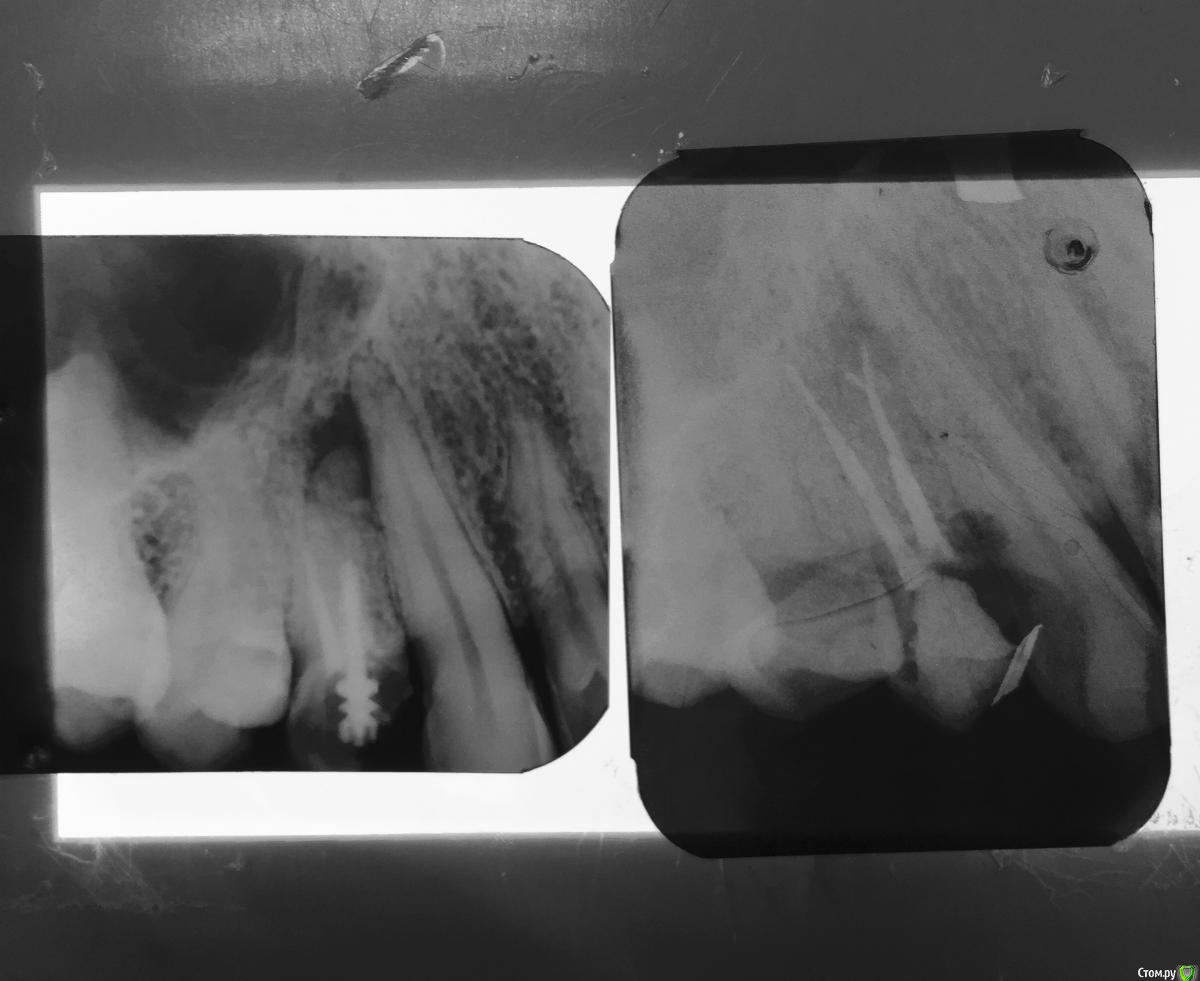

Kolchanov Опубликовано 5 ноября, 2016 Автор Поделиться Опубликовано 5 ноября, 2016 (изменено) Ренальду бальзам.Не стал полосочковать зуб. http://s017.radikal.ru/i436/1611/02/9146c4773490.jpghttp://s50.radikal.ru/i130/1611/bf/0fa817238bcc.jpghttp://s019.radikal.ru/i608/1611/3f/5810e9fa0ffd.jpghttp://s018.radikal.ru/i507/1611/ca/2f6f81f317cb.jpghttp://i075.radikal.ru/1611/63/3f27bba60ba3.jpghttp://s020.radikal.ru/i713/1611/b3/4b09d9693c50.jpgПациенткой озвучено было, что 25 лет назад лечен (даже если половиная этого срока, то меня устраивает). В полости зуба плотный фосфат, без признаков подтекания. Короче, вначале идя на ретрит, я по ходу переобулся и просто забилдапил. Ничего я там не смог бы улучшить... Изменено 5 ноября, 2016 пользователем Kolchanov Ссылка на комментарий

Kolchanov Опубликовано 12 января, 2017 Автор Поделиться Опубликовано 12 января, 2017 Зуб был не так давно по типу, как Каплан тут показал - http://forum.stom.ru/topic/34371-2017/?p=572789Пропущенный ММ канал со своим выходом посередке корняhttp://s013.radikal.ru/i323/1701/f5/68d652996212.jpghttp://s018.radikal.ru/i500/1701/b8/7c6205bbcf46.jpghttp://s020.radikal.ru/i716/1701/db/06ef1c465c7b.jpghttp://s019.radikal.ru/i626/1701/52/bf4b437a8455.jpghttp://s41.radikal.ru/i093/1701/76/3d73852c2a04.jpghttp://s001.radikal.ru/i193/1701/71/bb47b32b6958.jpg Обострение получил после первого визита. Резали и т.д. 3 Ссылка на комментарий

Kolchanov Опубликовано 12 января, 2017 Автор Поделиться Опубликовано 12 января, 2017 Сегодняшний зуб. Кажется я понял чего Соломонов советует СВШ на СИЦ фиксировать http://s020.radikal.ru/i705/1701/7e/12baaf0019d9.jpghttp://s018.radikal.ru/i500/1701/ce/28f347e5a0fa.jpgДействительно, вытаскивать гораздо проще. Гораздо! Главное не перепилить. Молодец Михаил Соломонов! Дельный совет!http://i066.radikal.ru/1701/88/70647ef634a0.jpgТеперь титанчик отпесоченный будет.http://s019.radikal.ru/i612/1701/60/8778e0c1ac33.jpghttp://s020.radikal.ru/i711/1701/ff/16af60074b3d.jpg 3 Ссылка на комментарий

Kolchanov Опубликовано 17 января, 2017 Автор Поделиться Опубликовано 17 января, 2017 Во какой достал. Редкий штифт!http://s020.radikal.ru/i702/1701/fd/6a675b5cea25.jpghttp://s019.radikal.ru/i632/1701/c4/34969c5b5257.jpg 2 Ссылка на комментарий